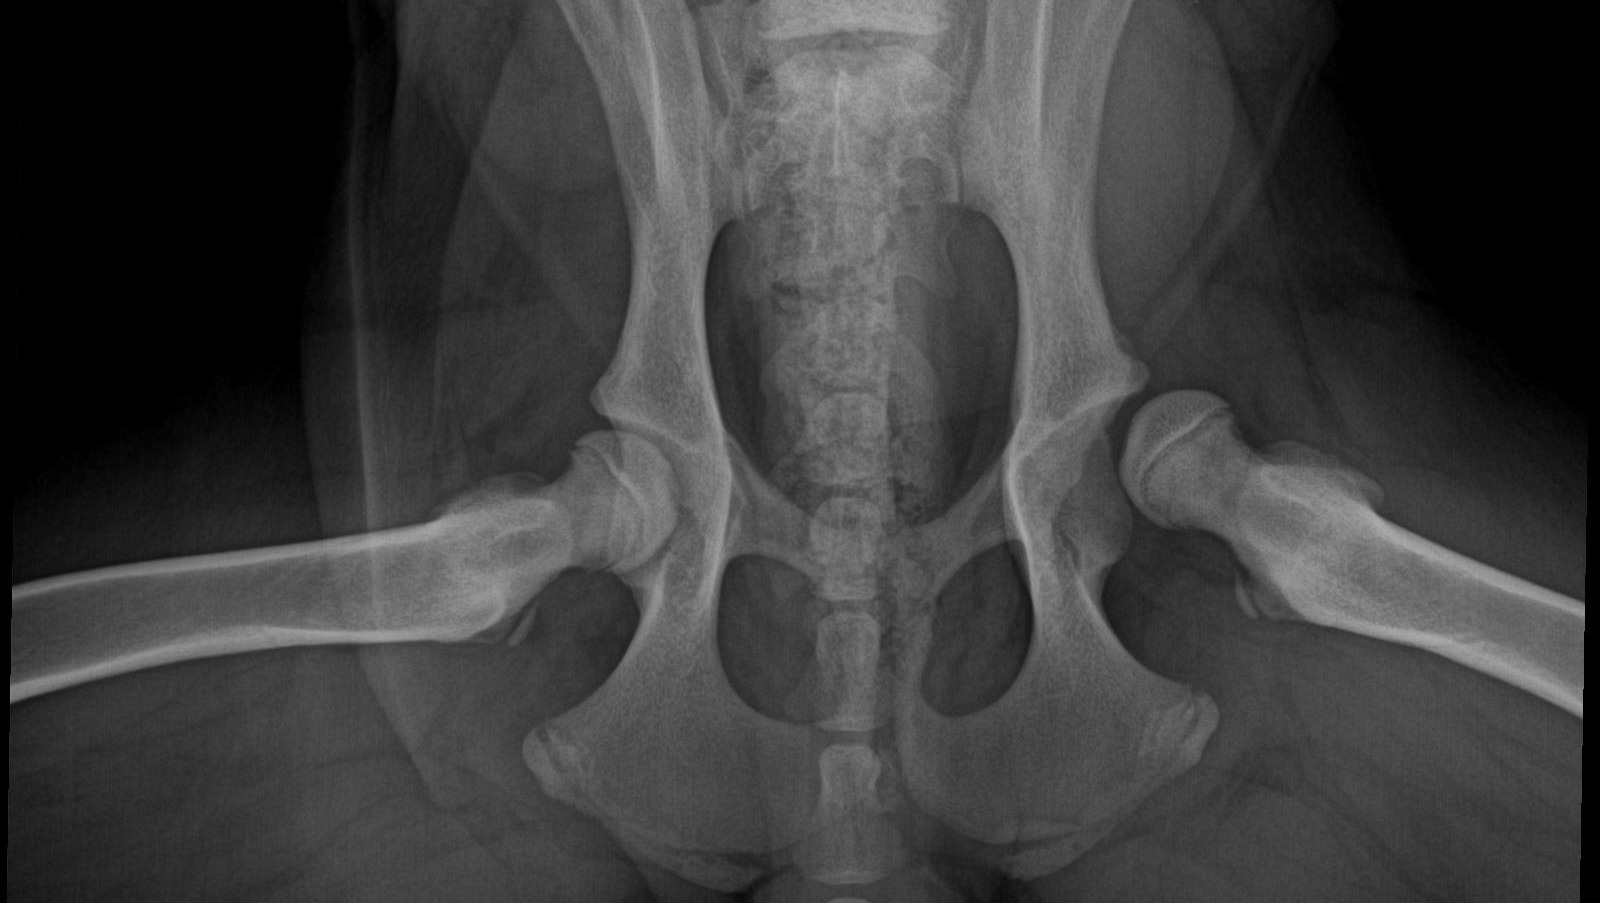

Un paio di mesi fa i miei genitori (non sono i miei veri genitori: sono solo due che mi hanno raccolto un giorno e non mi hanno più lasciato andare) si sono accorti che camminavo in modo bizzarro. Mia madre dice sempre che cammino come “due persone in un costume da cavallo”. Così mi hanno portato dal veterinario e hanno scoperto che i miei veri genitori mi hanno trasmesso la displasia dell’anca. Bilaterale e molto molto grave. Nessuno sapeva molto di loro perchè sono stato ritrovato con mio fratello sul ciglio della strada. Anche lui ha la displasia. Ma anche questa è un’altra storia.

Non abbiamo un preventivo ufficiale da caricare perchè non siamo ancora certi della cifra esatta che dovremo spendere. Il costo della protesi d'anca varia da 3300 a 3800 euro più IVA per anca (in funzione delle dimensioni degli impianti) e comprende gli impianti in titanio, l'intervento, le radiografie post-operatorie ed il ricovero di 24 ore con le relative cure. Eventuali radiografie pre-operatorie per cani non già sottoposti ad una visita preliminare della clinica che lo opererà (che è il nostro caso), saranno da conteggiare a parte.

Scopriremo pertanto il costo delle protesi la mattina stessa dell'intervento: andrà dai 4.026 € ai 4.636 € per gamba, per cui in totale da 8.052 a 9.272 € più il costo delle radiografie pre operatorie che non conosciamo ma che nella nostra esperienza varia tra i 200 e i 350 euro.

My mom said I walk like “two people in a horse costume”. So they took me to the vet and found out that my real parents gave me hip dysplasia. Bilateral and very bad. Nobody knew much about them because I was found with my brother on the side of the road. He has dysplasia too. But this again is another story.